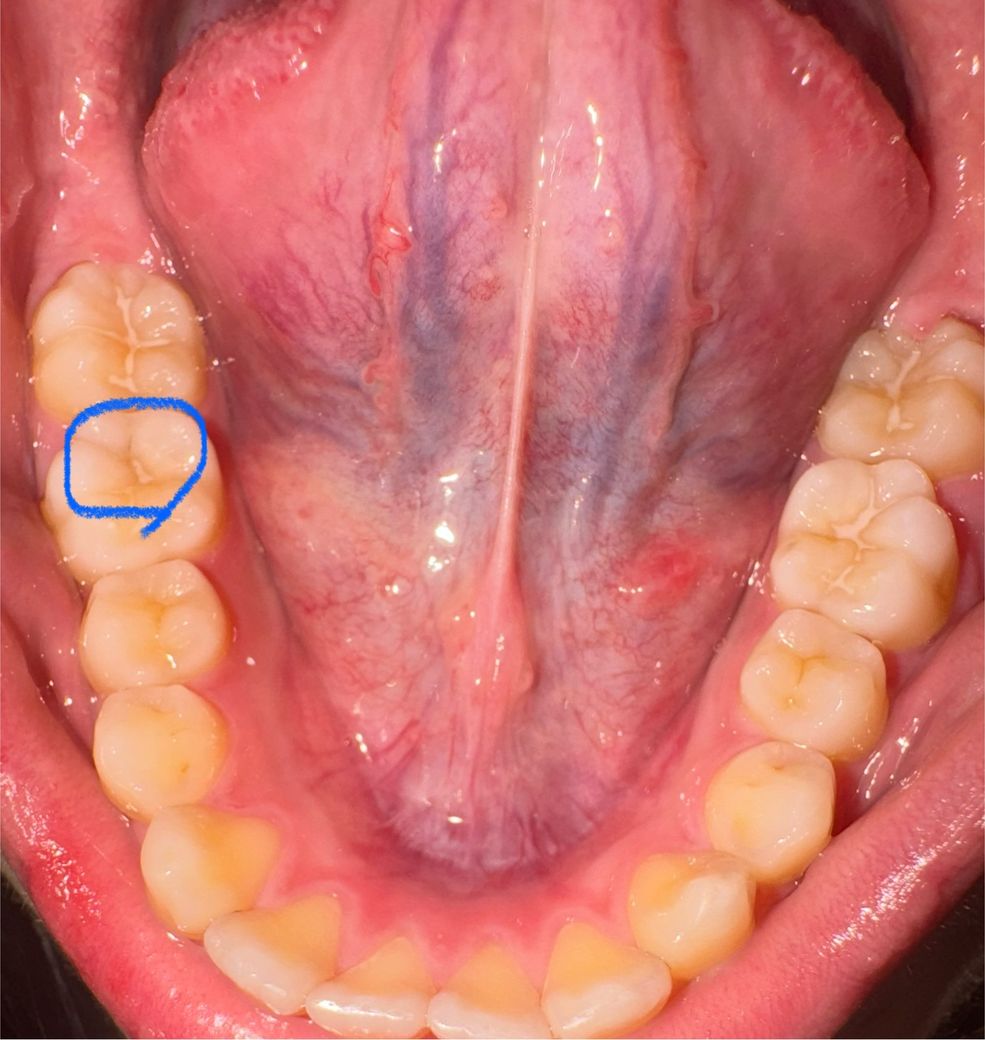

어금니에 충치가 생긴건지 궁금합니다

실란트를 7년? 전에 했는데

이 부분 실란트가 떨어져 나간건지

착색된건지

충치인지 궁금합니다

• 1번 째 사진

일부 떨어진 부위도 보이고 착색이 아닌 충치가 나타난 것으로 보여집니다. 현재 사진으로 보아서는 그 충치가 커 보이지 않으며 간단한 레진 등으로 치료가 가능할 것으로 보입니다. 더 커지기 전에 충치 부위를 제거하고 레진 등으로 치료하는 것을 권해드립니다.

사진만으로는 약간 애매한 부분이 있어 해당 부분은 치과 내원하셔서 검진 받으시는게 좋아보입니다. 변연 일부 변색되며 보이는 부분도 있는 것 같으며 우식도 일부 있을 가능성도 있어 보이기도합니다. 자세한건 검진 꼭 받아보시기를 권유드립니다.

일부실란트는 떨어져 나간 것 같고 충치로도 보입니다 치과가서 정확히 탐침으로 긁으며 검사해봐야합니다